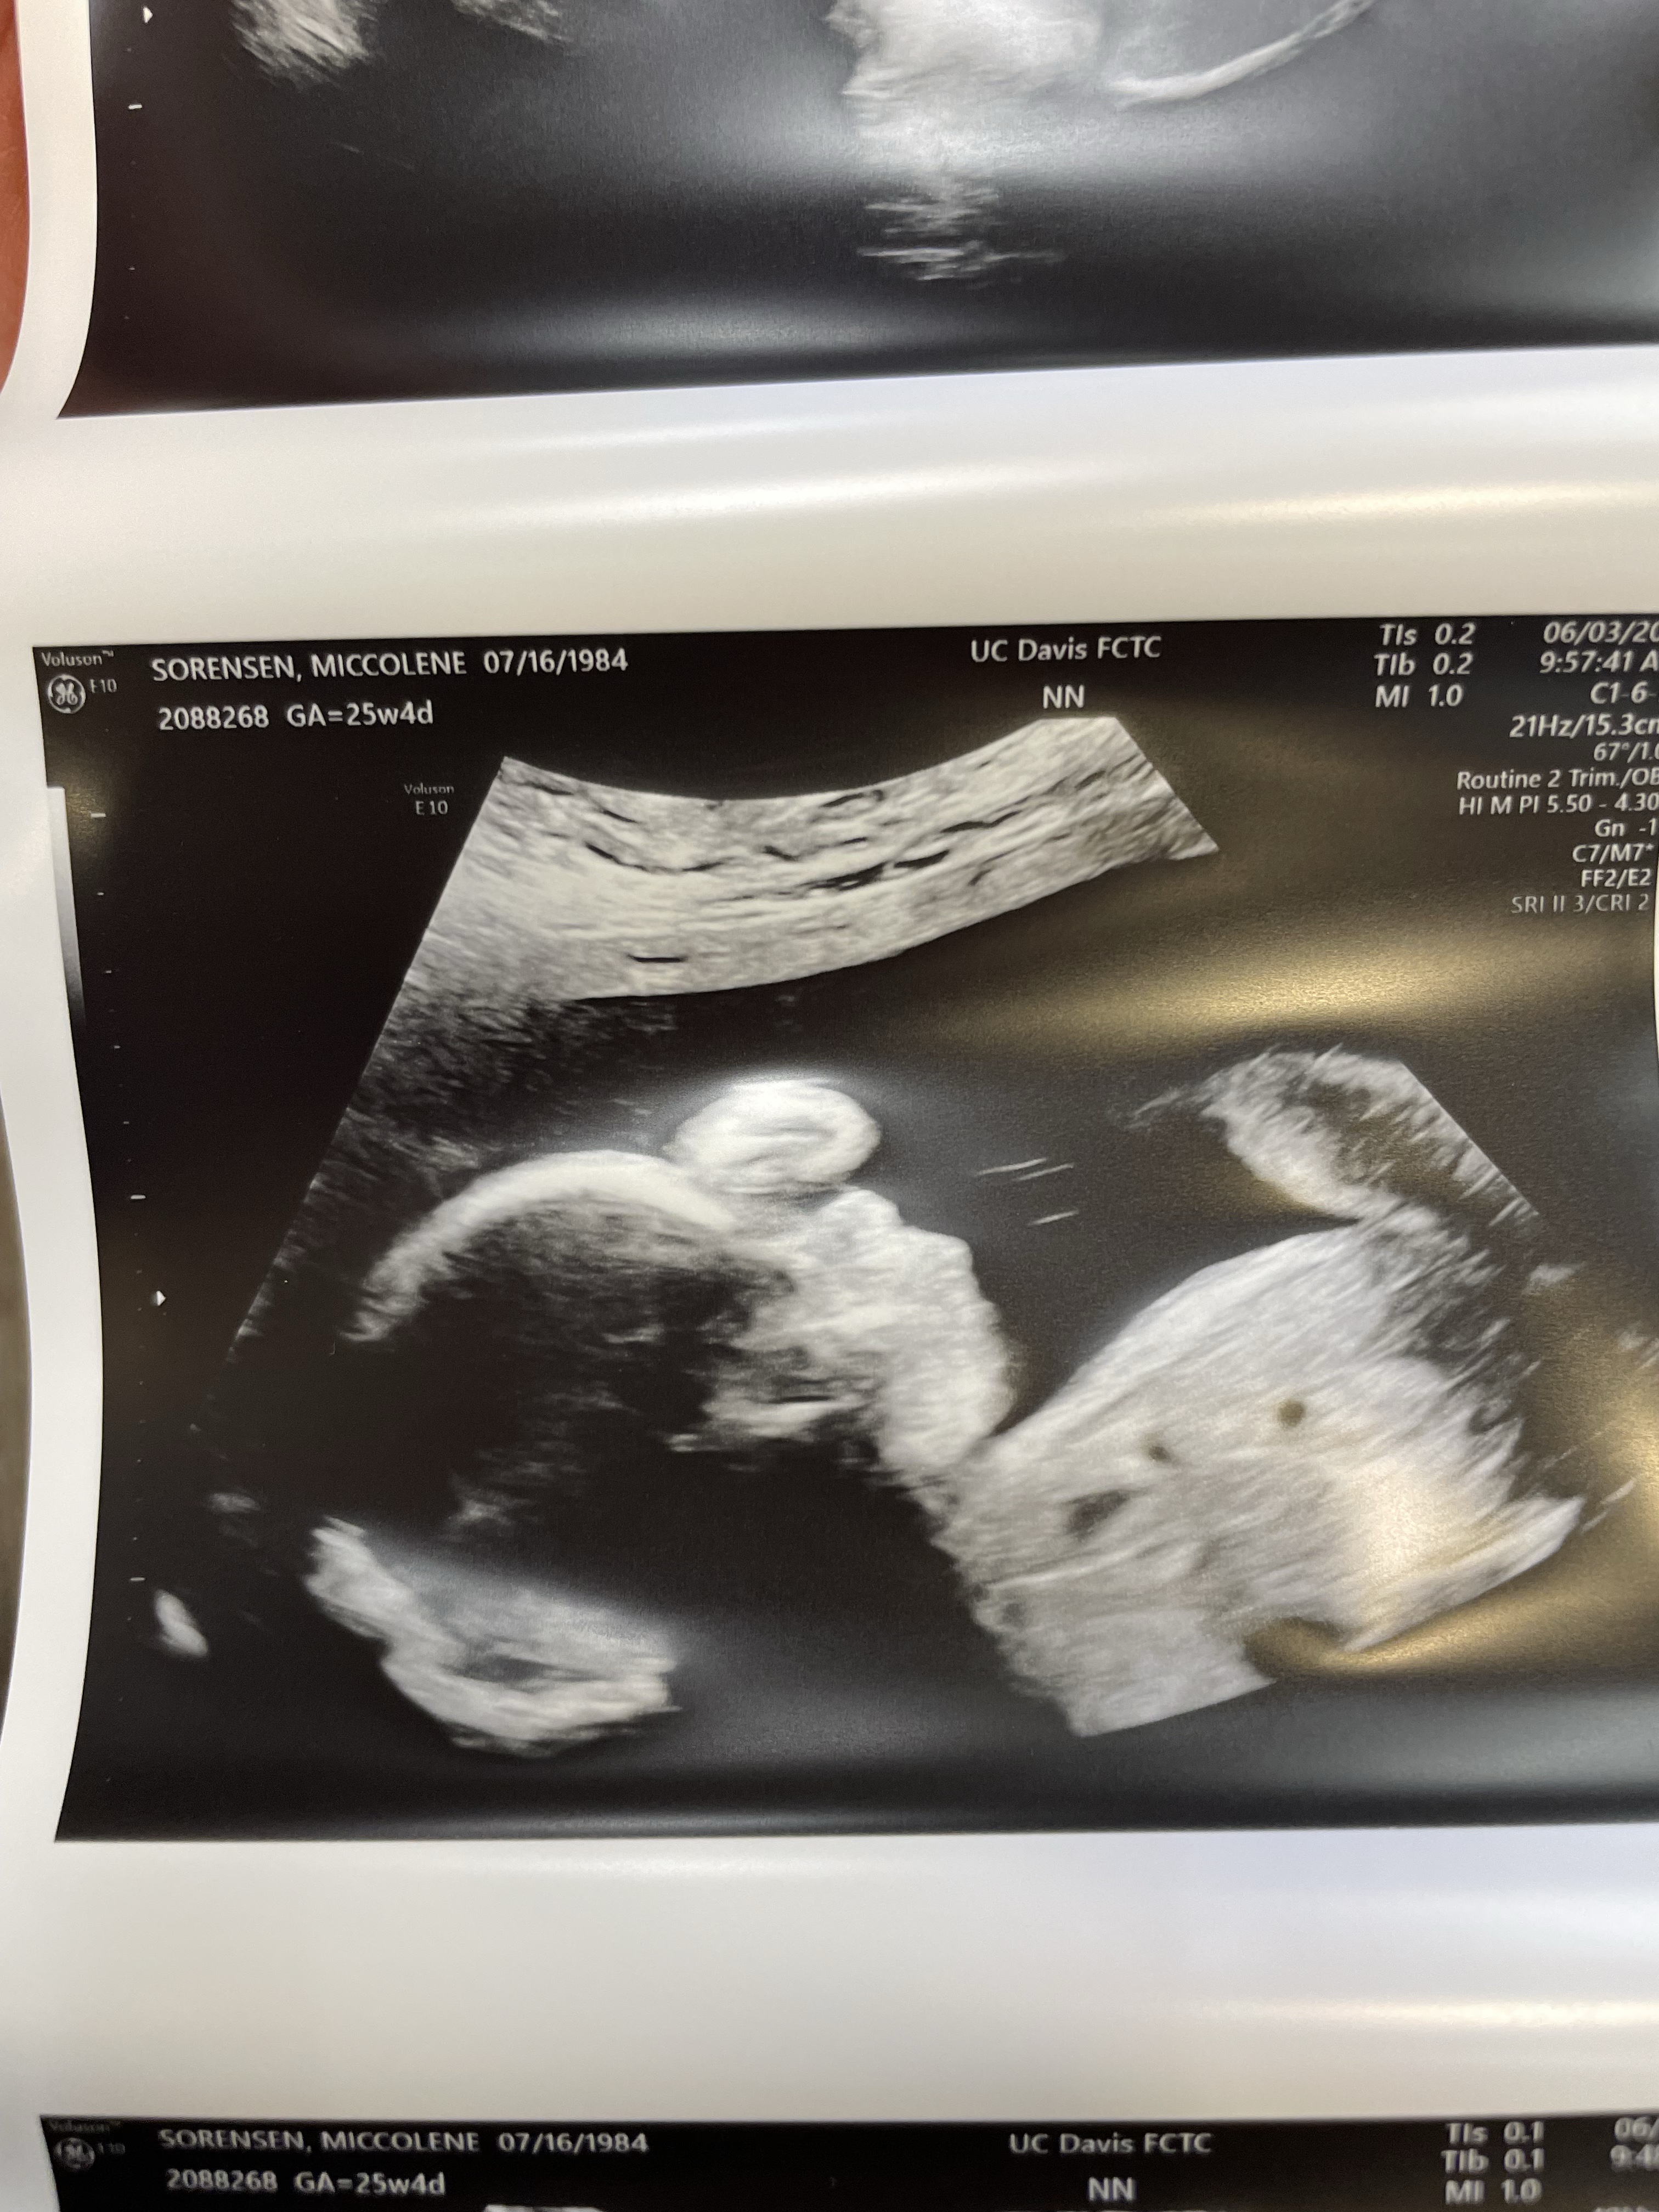

The first week of June we drove down to UC Davis for our fetal echo and anatomy scan. We waited a long time for this appointment, I think I was something like 26 weeks along when we finally got it down. I was thrilled to confirm that she is indeed a lady baby and soooo relieved that her anatomy scan looked perfect. I was so nervous to talk to the pediatric cardiologist, but he said she looks great. So much relief. She was measuring right on track, perfectly healthy.